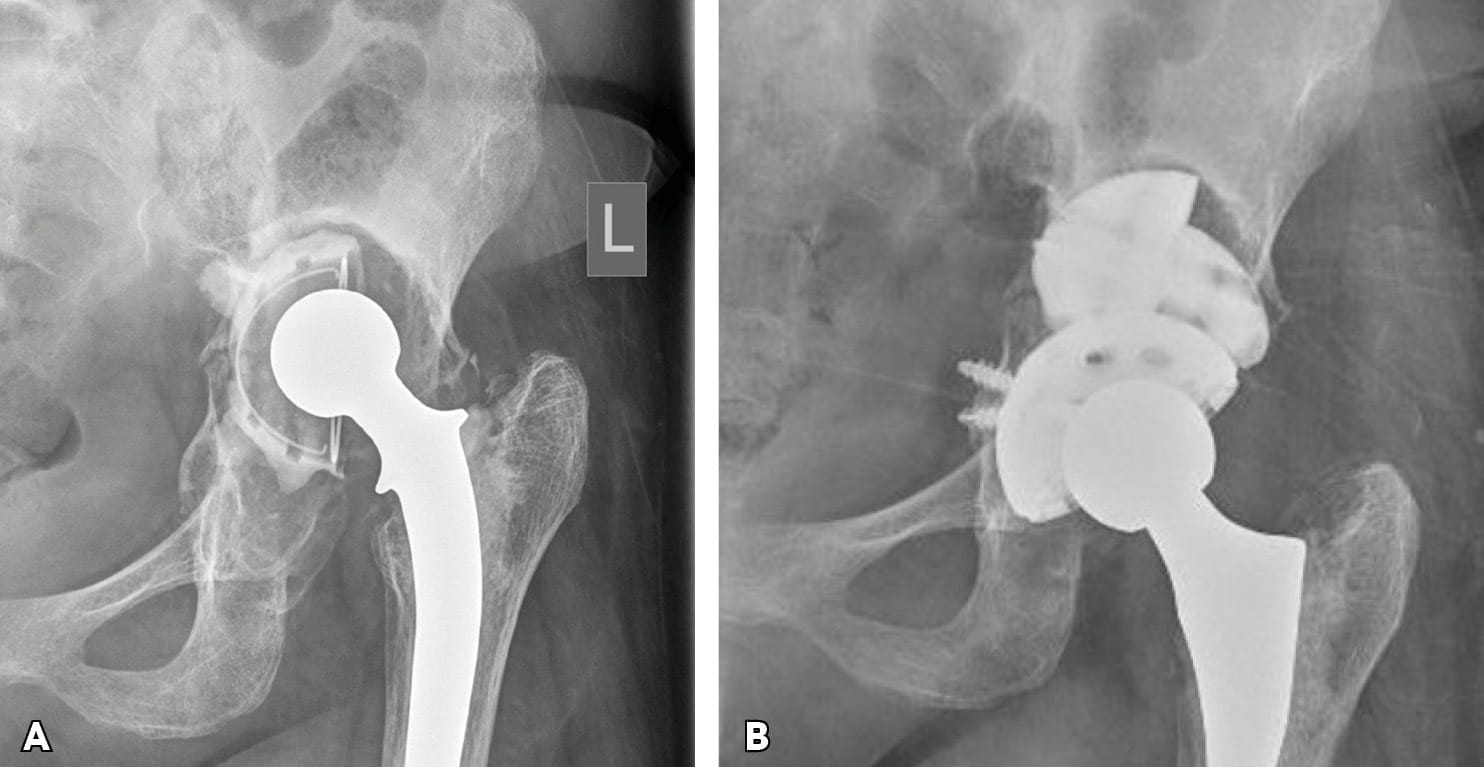

A classification system should accurately describe the problem, assist pre-operative evaluation and surgical pre-operative planning, and should predict outcomes. The recent Sen et al classification of late post-traumatic acetabular defects clearly reveals the patterns of post-traumatic nonunions and malunions.[1] Sen RK, Mukhopadhyay R, Pattanshetti V, Saini G, Tripathy SK, Sethy SS, Sharma SK. A New Classification System for Acetabular Bone Defect Evaluation in Posttraumatic Acetabular Nonunion and Malunion. Indian J Orthop. 2022 Jun 27;56(9):1601-1612 In the commonly used Paprosky classification, PD is often associated with IIIB and infrequently with IIC and IIIA bone defects.[4] Paprosky WG, Perona PG, Lawrence JM. Acetabular defect classification and surgical reconstruction in revision arthroplasty. A 6 year follow up evaluation. J Arthroplasty. 1994;9(1)33-34. However, the Paprosky classification fails to describe post-traumatic defects, and occasionally, orthopaedic surgeons encounter other acetabular bone defects which are not described by existing classification systems (Figure 1).

Cages and Rings with graft. Historically, massive bulk allograft, used with a cemented liner in the setting of severe bone defects had a 50% failure rate.[8] Garbuz D, Morsi E, Gross AE. Revision of the acetabular component of a total hip arthroplasty with a massive structural allograft. Study with a minimum five years follow up. J Bone Joint Surg Am. 1996; 78:693-697. In the past, reconstruction cages and rings have also been used extensively to reconstruct severe acetabular bone defects and PD. Structural or morsellised bone allografts were used in order to fill the acetabular defect and then a cage or ring was used to protect the grafted area until the allograft was incorporated by creeping substitution. Acetabular components were then cemented in an appropriate orientation. Several manufacturers have developed various ilioiscial (onlay or inlay) or non-ilioischial spanning cages and rings. However, despite reports of early satisfactory outcomes, many of these devices were later withdrawn due to subsequent mid- and long-term failures (Figure 5a).[9], Regis D, Sandri A, Bonetti I, Bortolami O, Bartolozzi P. A minimum of 10 year follow up of the Burch-Schneider cage and bulk allografts for the revision of pelvic discontinuity. J Arthroplasty. 2012; 27:1057-1063.e1.[10] Abolghasemian M, Tangsaraporn S, Drexler M, Barbuto R, Backstein D, Safir O, Kuzyk P, Gross A. The challenge of pelvic discontinuity: cup-cage reconstruction does better than conventional cages in mid-term. J Bone Joint Surg Br. 2014; 96-B(2):195-200.

Tantalum cementless acetabular cups with augments. TM and related (e.g. Cription) technology acetabular components fixed with multiple holes superiorly and inferiorly (ilium, pubic and ischial rami) in combination with augments have recently been used in severe acetabular defects and chronic PD, especially in those with good bone stock (Figure 5b).[14] Batuyong ED, Brock HS, Thiruvengadam N, Maloney WJ, Goodman SB, Huddleston JI. Outcome of porous tantalum acetabular components for Paprosky type III and IV defects. J Arthroplsty. 2014; 28: 1318-1322. Implants made of highly porous structural materials (e.g. Tantalum and Cription) have demonstrated an improved friction coefficient for initial stability and better bony ingrowth for late stability. Early and mid-term outcomes are encouraging, allowing for extending the indications for their use (Figure 6).[15] Jenkins DR, Odland AN, Sierra RJ, Janssen AD, Lewallen DG. Minimum dive year outcomes with porous tantalum acetabular cup and augment construct in complex revision total hip arthroplasty. J Bone Joint Surg Am. 2017; 99:e49.